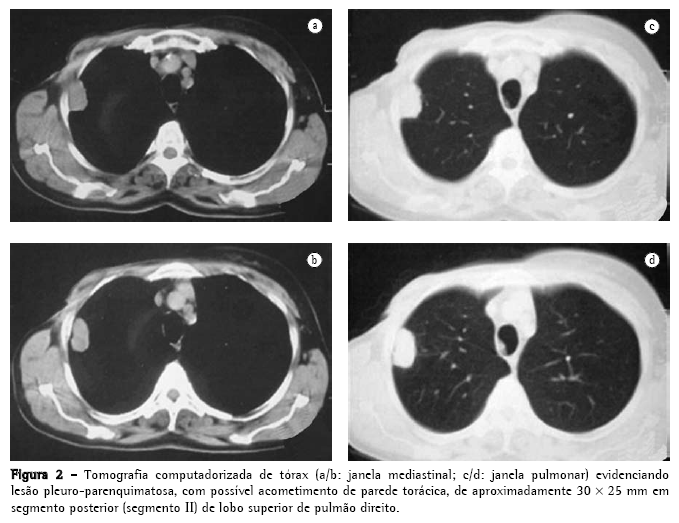

Paciente do sexo feminino, 60 anos, branca, em menopausa há 14 anos, é encaminha devido à presença de nódulo pulmonar à radiografia de tórax (Figura 1) diagnosticado no seguimento pós-operatório por neoplasia de mama. Trata-se de uma paciente que tem como antecedente pessoal a realização de mastectomia total à direita e linfadenectomia axilar ipsilateral há 3 anos por carcinoma ductal invasivo (diagnosticado por core biopsy) de 45 mm em seu maior eixo, grau nuclear II e estádio IIB (T2N1Mx). Submetida também à hormonioterapia (tamoxifeno 20 mg/dia) e quimioterapia (ciclofosfamida + metrotexate + 5-fluorouracil: quatro ciclos neoadjuvantes e seis ciclos adjuvantes), assim como a radioterapia adjuvante (dose total de 50 Grays por cinco semanas). Negava sintomas pulmonares, febre e emagrecimento.

Foi então realizada tomografia computadorizada de tórax que identificou um nódulo pulmonar pleuro-parenquimatoso de aproximadamente 30 × 25 mm (Figura 2) em pulmão direito. Assim foi aventada a hipótese de metástase pulmonar do carcinoma de mama previamente operado, sendo indicada biópsia para confirmação diagnóstica.